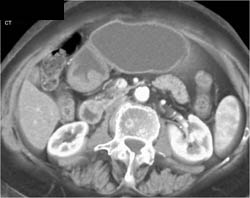

Antral Carcinoma